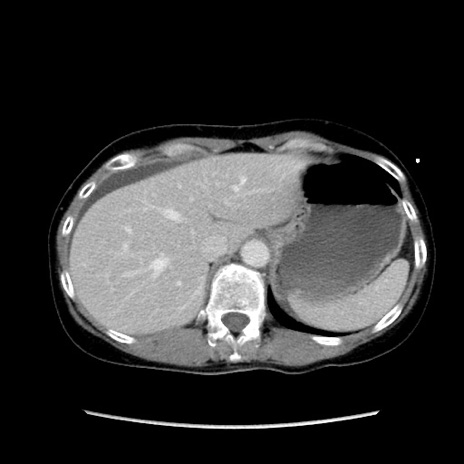

症例32(横断像)

【症例】40歳代 女性

【主訴】上腹部痛、嘔気・嘔吐

【現病歴】約9時間前頃から急に上腹部痛、嘔気、嘔吐が出現。改善しないため救急要請。

【既往歴】子宮頚癌(広汎子宮全摘術、放射線療法)、腸閉塞

【身体所見】腹部:平坦、軟、腸雑音亢進、上腹部を中心に腹部全体に圧痛あり。

【データ】WBC 8400、CRP 0.03